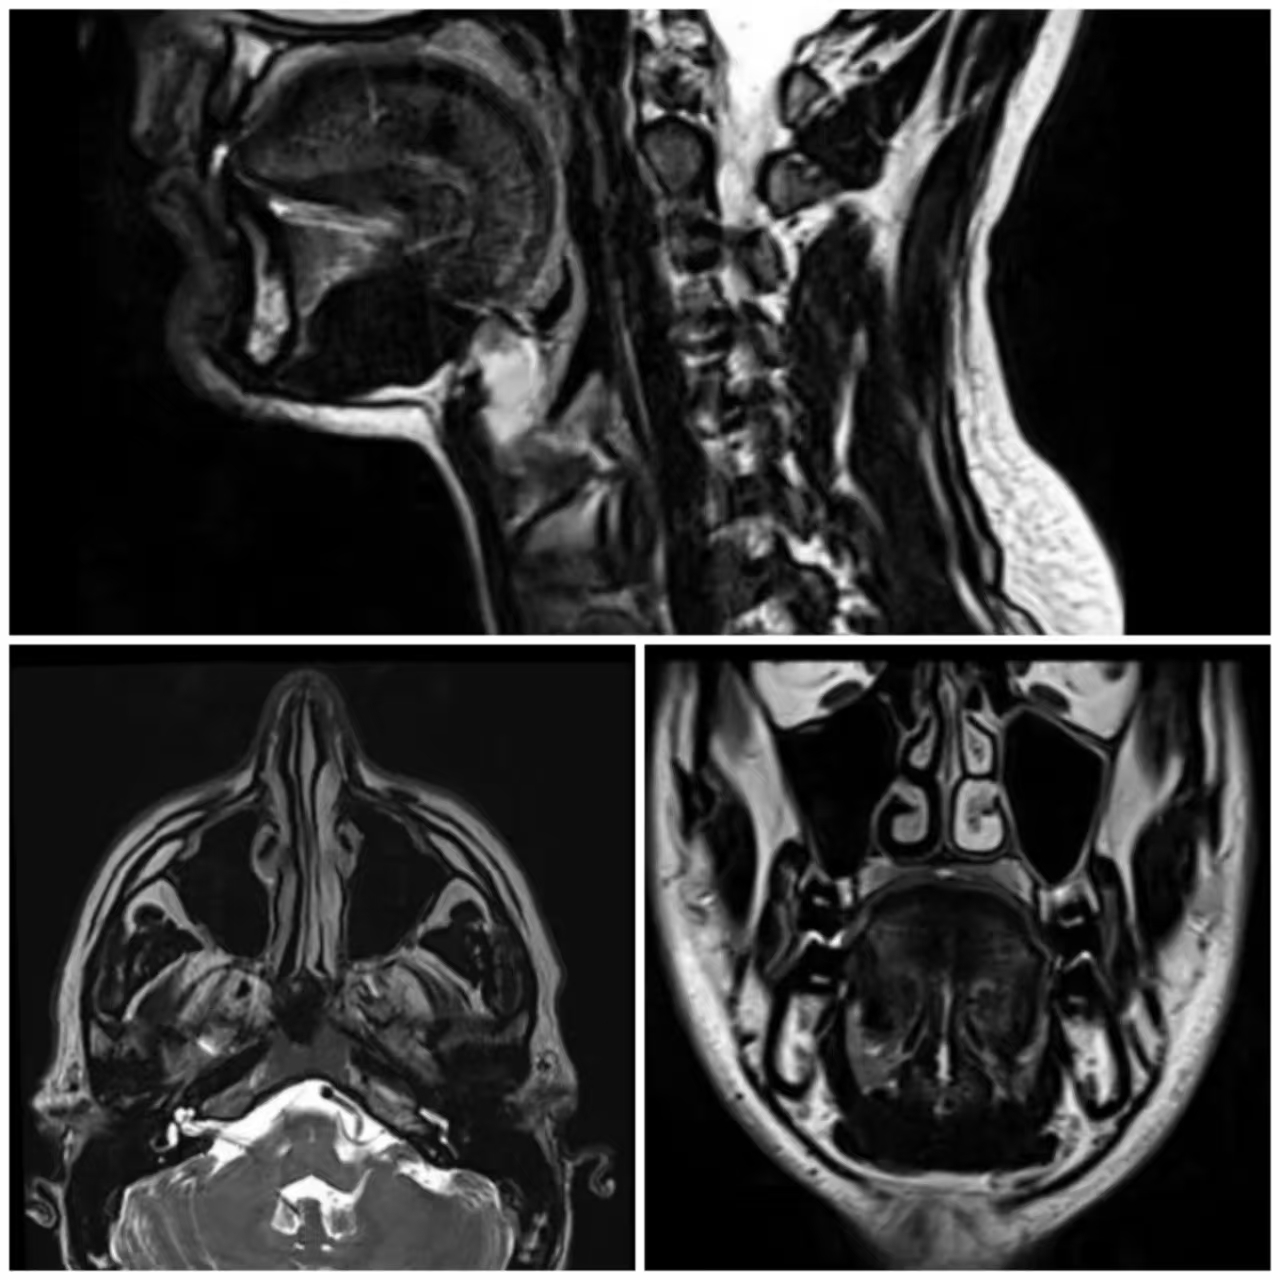

3. 多方位成像,全面覆盖病变范围

MRI可实现轴位、冠状位、矢状位多平面成像,从多角度完整呈现鼻窦结构及病变,弥补单一视角局限,降低漏诊风险。对鼻窦深部隐匿炎症及向颅内、眼眶侵犯的病变,能清晰明确累及范围,提供全面诊断信息。